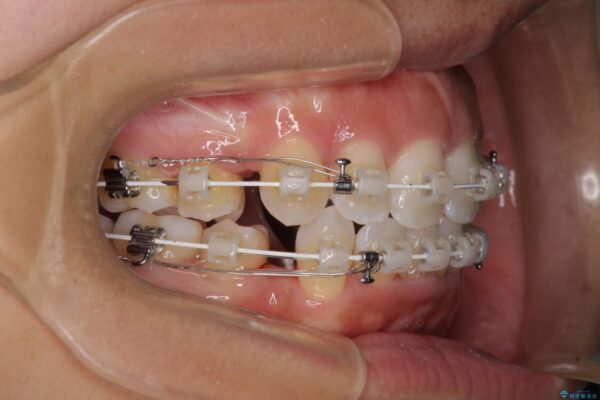

治療途中

審美装置